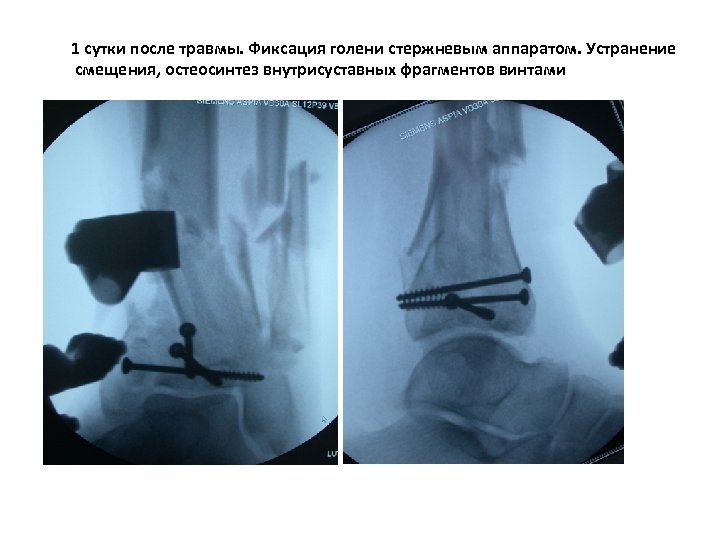

Больной с многооскольчатым, внутрисуставным переломом нижней трети костей голени со смещением отломков

1 сутки после травмы. Фиксация голени стержневым аппаратом. Устранение смещения, остеосинтез внутрисуставных фрагментов винтами